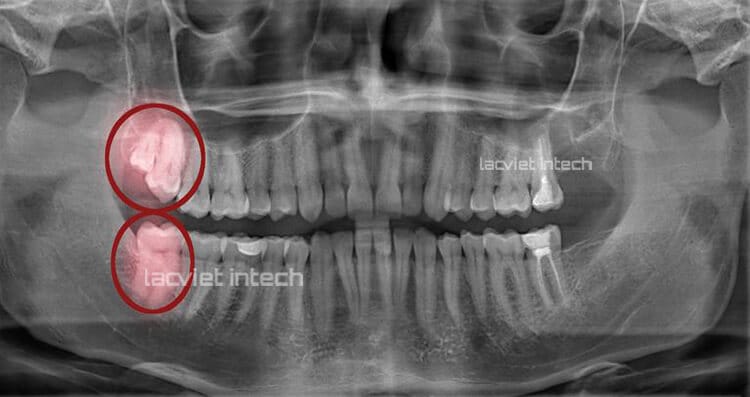

Trong trường hợp mọc răng khôn, bác sĩ sẽ chụp X-quang để theo dõi tình trạng răng có mọc lệch không? Nếu có, sẽ sắp xếp lịch nhổ răng sớm để tránh ảnh hưởng đến răng khác cũng như sức khỏe tổng quát.